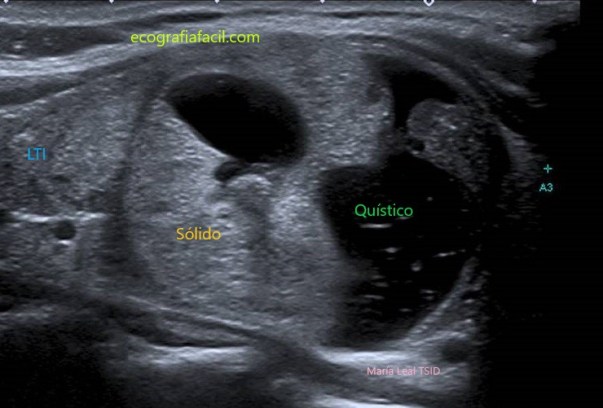

SÓLIDO QUÍSTICO:

Nódulo sólido-quístico